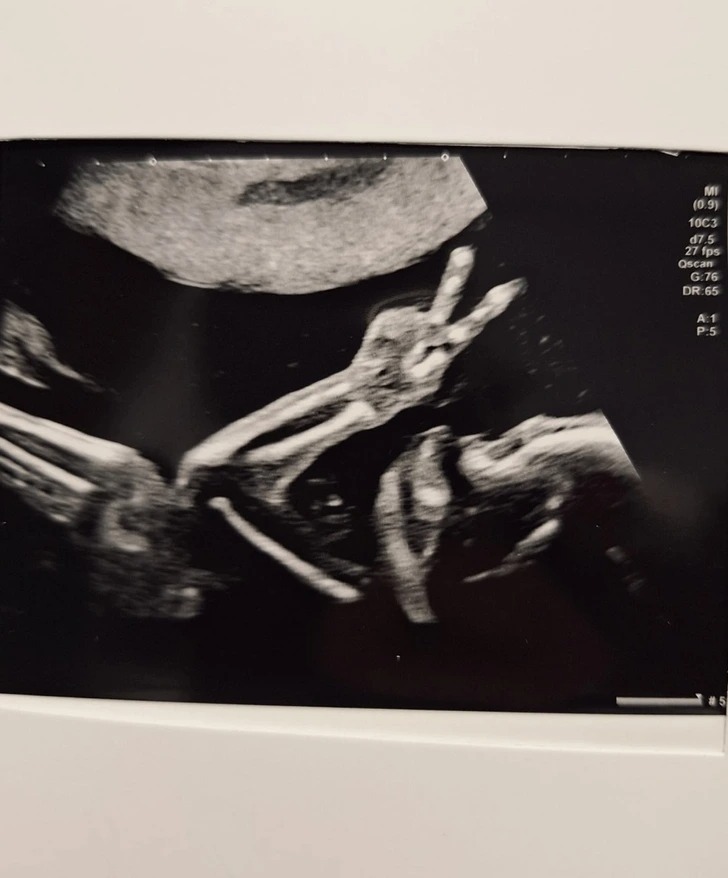

«Моїй сестрі 20 тижнів. Вона гралася зі своїми пальцями»